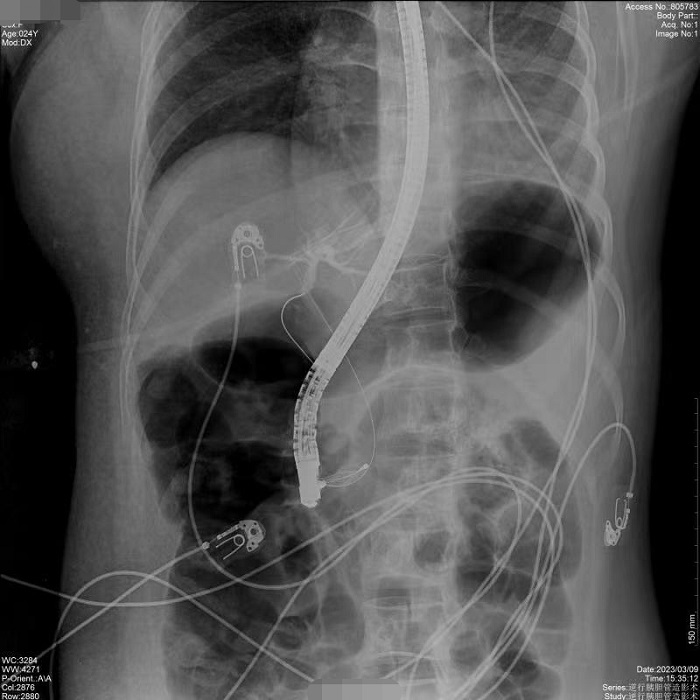

病例1:患者間斷上腹部脹痛4月,經(jīng)磁共振膽道水成像(MRCP)明確為膽總管結(jié)石、膽囊結(jié)石。常規(guī)手術(shù)需要膽總管切開(kāi)取石,考慮其自身的訴求,醫(yī)生決定嘗試為患者做內(nèi)鏡逆行膽管造影術(shù),幫助實(shí)現(xiàn)最小創(chuàng)傷及快速康復(fù)。術(shù)中,通過(guò)十二指腸鏡,將導(dǎo)絲通過(guò)十二指腸乳頭(即膽總管的下端開(kāi)口處)置入膽管內(nèi),在X線透視下注射造影劑造影,完成對(duì)膽總管內(nèi)情況診斷,并在診斷基礎(chǔ)之上完成取石治療。